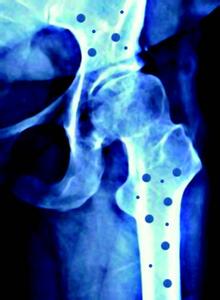

软骨病又称骨软化病,是成人严重缺钙的结果,多见于多次妊娠、多产的妇女及体弱多病的老人。

成人骨骼也存在骨钙化和骨吸收这两个过程,微量元素检测仪即既有钙磷等无机物不断地沉积于骨组织中,又有骨钙的溶出,是一个不断发生新陈代谢的平衡体系。当机体长期、严重的钙缺乏,导致一方面机体不能正常进行骨的钙化,而另一方面又不断进行骨吸收,久而久之就出现骨软化。

青年妇女由于生育和哺乳需要大量的钙,微量元素检测仪厂家分析如果未能及时补充,不仅不能进行正常的骨钙化,还会加快骨的吸收,使骨骼中矿物质减少;加上多次妊娠、哺乳,骨骼脱钙越来越严重,就可能导致软骨病。软骨病最常见的症状是骨痛、肌无力和骨压痛,有时候也有肌痉挛及手足抽搐;或表现为骨质软化、容易变形,孕妇骨盆变形可致难产。软骨症发病初期,骨痛部位不固定,多在腰背部或下肢,一般活动时加重,常被认为是风湿或神经官能症。肌无力也是一个重要表现,开始是上楼梯后从坐位起立很吃力,提不起重物,脊柱弯曲,病情加剧时完全不能行走,卧床不起。在骨痛与肌无力同时存在的情况下,患者走路时步态特殊,呈摇摆扭动,称为“鸭步”或“企鹅步”。骨压痛多见于胸骨、肋骨、盆骨及大关节处,不能碰触,稍触之即疼痛难忍。四肢弯曲变形,可有自发性骨折。患者的心肺等内脏功能也可能同时受损。